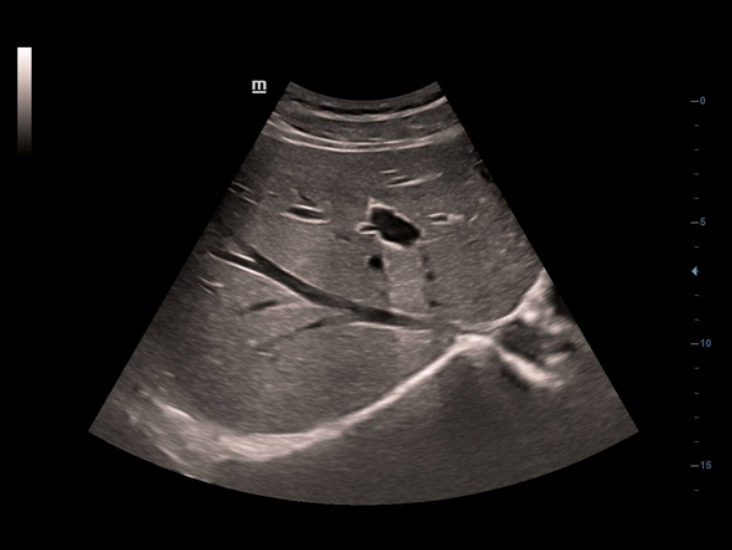

Poprzez zastosowanie klasycznych technologii obrazowania, wykorzystywanych w uznanych systemach ultrasonograficznych, DC-40 Full HD dostarcza doskonale szczeg├│?owy obraz.

- iClear (technologia redukcji zak?óceń obrazowania)

- PSH (obrazowanie harmoniczne z odwr├│ceniem fazy)

- iBeam (technologia obrazowania z wykorzystaniem skrzy?owanych ultrad?wi?k├│w)